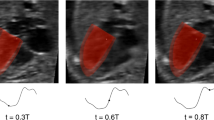

2.3 Image processing

For patient-specific FE simulation of both pre-FAV and post-FAV LVs, 3D reconstructions of the LV myocardium, left atrium (LA) cavity and right ventricle (RV) cavity were first performed as previously reported (Green et al. 2022). Briefly, 2D slices were extracted from the 4D volume files, and then, binary segmentation of the myocardium was performed using a lazy snap algorithm (Li et al. 2004). 3D reconstruction was then performed with VMTK (www.vmtk.org), with the reconstructed geometries smoothed in Geomagic (Geomagic Inc., Morrisville, NC, USA). 3D motions of the LV, LA and RV were extracted using a validated cardiac motion estimation algorithm (Wiputra et al. 2020). The algorithm modeled motion in the image with spatial b-splines of temporal Fouriers, and was curve-fitted to the displacement fields from 3D pair-wise registration images of consecutive time points. The final reconstructed LV geometries are depicted in Fig. 1, where satisfactory tracking can be demonstrated in Supplementary Fig. S1.

where LA capacitance was assumed based on the gestational age-specific value derived in the lumped parameter model (Pennati et al. 1997; Pennati and Fumero 2000). LV myocardium models, displayed in Fig. 1, were meshed with a minimum of 2500 quadratic tetrahedral elements, which was sufficient for mesh convergence as shown in our previous study (Ong et al. 2020). The formal FE simulation was performed by minimizing the weak formulation of a Lagrangian function described by Shavik et al., which enforced tissue stress equilibrium, incompressibility, and required a specific cavity volume to yield cavity pressure, using the Newton Solver in the FEniCS software (Shavik et al. 2018). The boundary conditions were like that previously reported (Shavik et al. 2018), with the basal plane of the LV constrained in the longitudinal direction and a weak 90 Pa spring applied to the entire epicardium at the load-free state, to constrain translational motion of the model and to imitate the behavior of the surrounding tissues. The model was executed for 30 cycles, to ensure steady state was achieved.